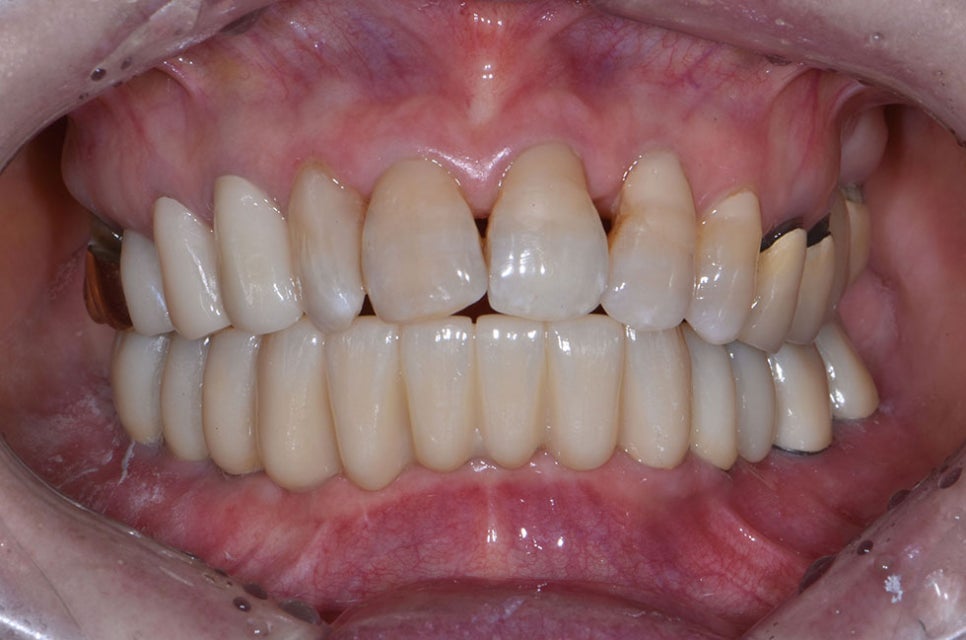

하루 최다 20개까지도 식립이 가능한

무치악 임플란트 즉 전체 임플란트의 경우

치료 기간을 단축하고 치아가 없어

나타날 수 있는 다양한 합병증들을

예방하는 데에도 좋은 치료 방법이 됩니다.

또한 개인의 뼈 상태에 따라 당일

치료가 어려울 수 있고 치료 기간도

달라질 수 있지만 별다른 문제가

없는 경우에는 치료를 받은 당일도

간단한 식사가 가능하며 회복이 빠른

장점이 있습니다.